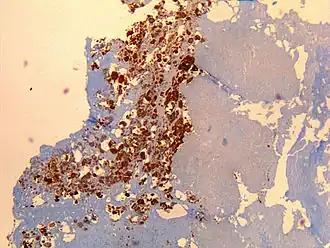

![]() Detección inmunohistoquímixa de Coixella burnetti en la válvula cardíaca de un hombre de 60 años | ||

El diagnóstico se basa principalmente en los exámenes serológicos[6][7] para hallar anticuerpos en contra del antígeno bacteriano en lugar de buscarlo. La detección molecular de ADN bacteriano es cada vez más usada. El cultivo es técnicamente difícil y no está disponible de forma rutinaria en la mayoría de los laboratorios de microbiología. La fiebre Q puede causar endocarditis (infección de las válvulas del corazón) que puede requerir Ecocardiografía transesofágica para ser diagnosticada. La hepatitis de la fiebre Q se manifiesta como una elevación de la Alanina aminotransferasa y del Aspartato aminotransferasa, pero el diagnóstico definitivo sólo es posible con una biopsia hepática, que muestra los característicos granuloma en anillo de fibrina.[8]